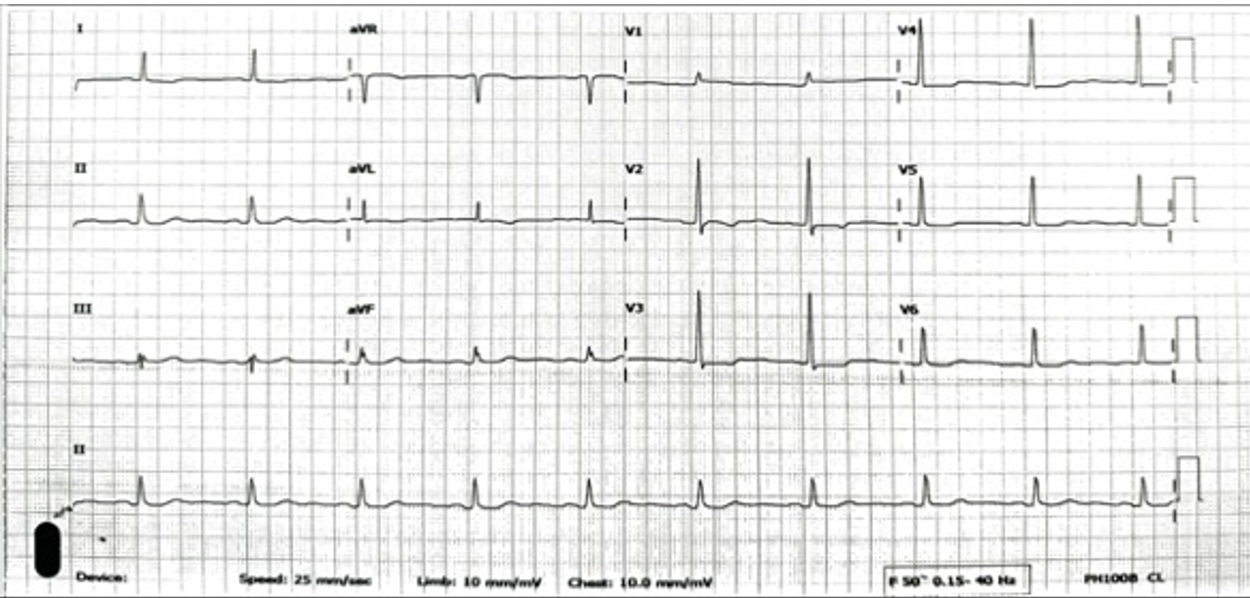

The initial electrocardiogram showed a sinus rhythm rate of 60 beat per minute with horizontal ST depression in V2 to V4. The transthoracic echocardiography demonstrated a left ventricular ejection fraction of 58% with anterior and anteroseptal wall hypokinesia from mid to apex and no significant valvular abnormalities. Basic laboratory results were normal.